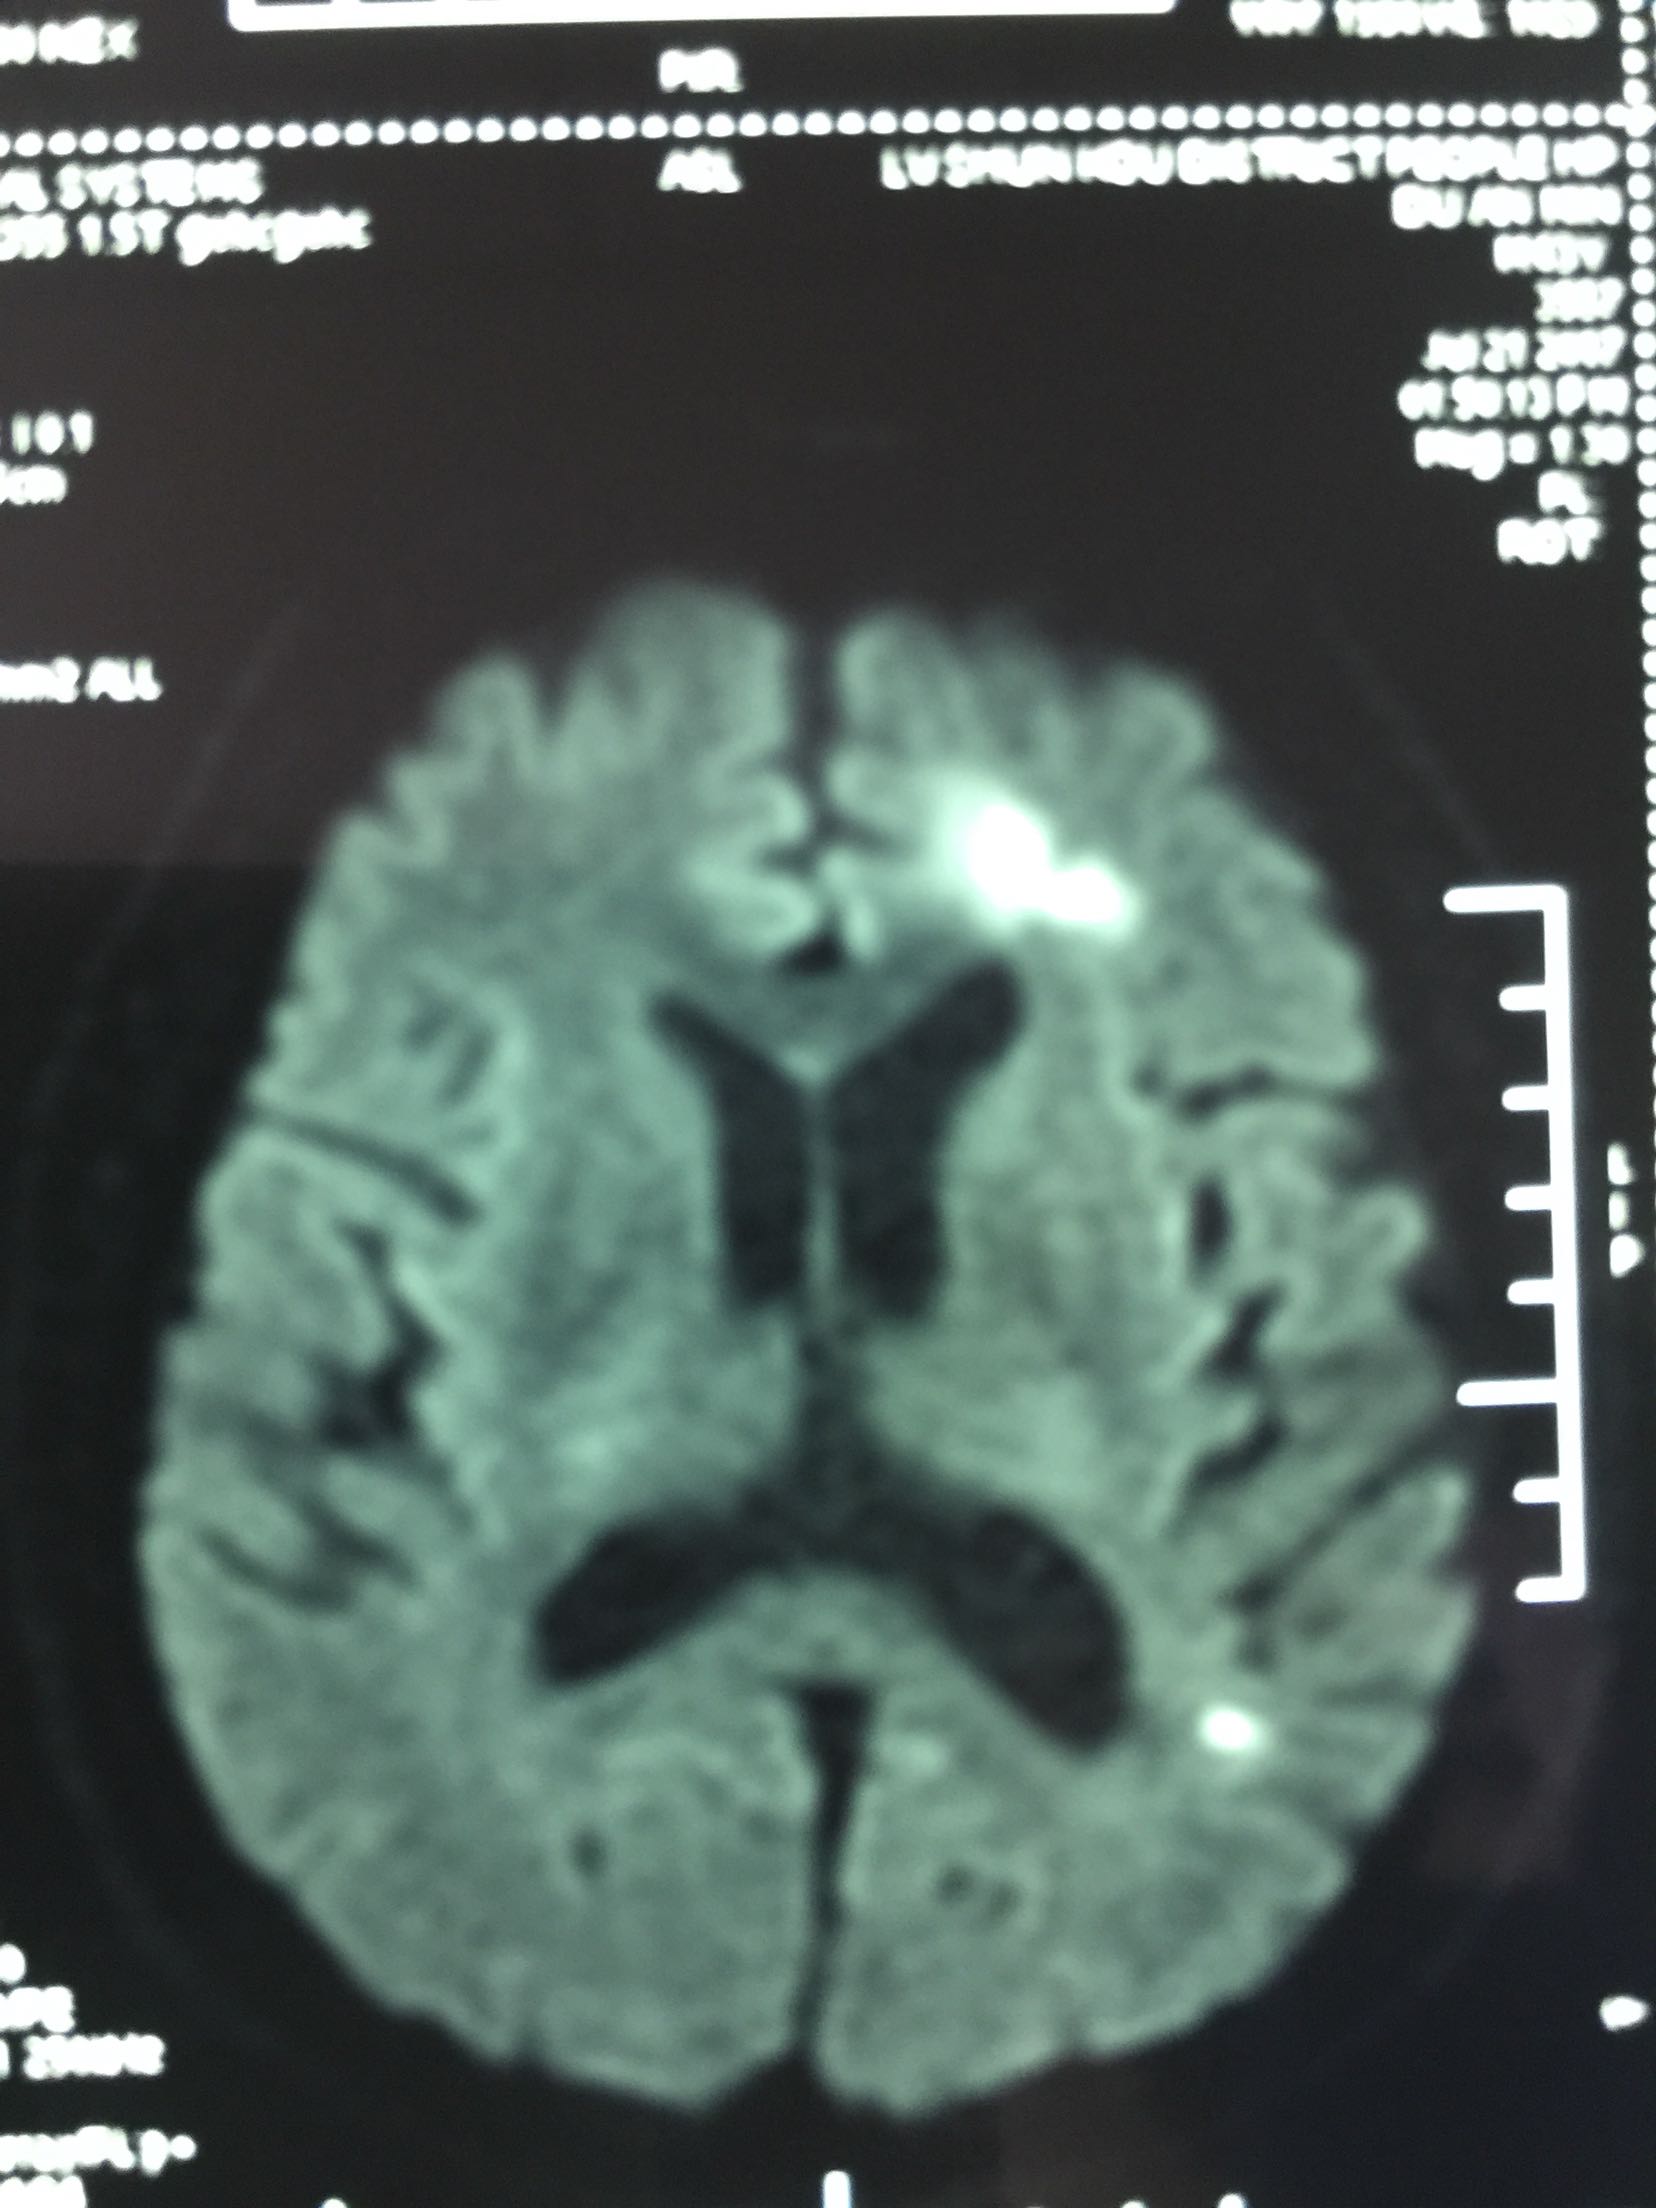

诊断:分水岭脑梗死 高血压病3级 急高危 治疗:吸氧 心电血压血氧监测 依达拉奉清楚自由基 长春西汀改善微循环 丁苯肽建立侧枝循环 阿司匹林 氯比格雷双抗 阿托伐他汀降脂稳斑

随访及预防:66岁男患,首先TIA发作,之后脑梗死,MRA可见左侧大脑中动脉狭窄,目前双抗血小板,联合大剂量他汀,未再发作。